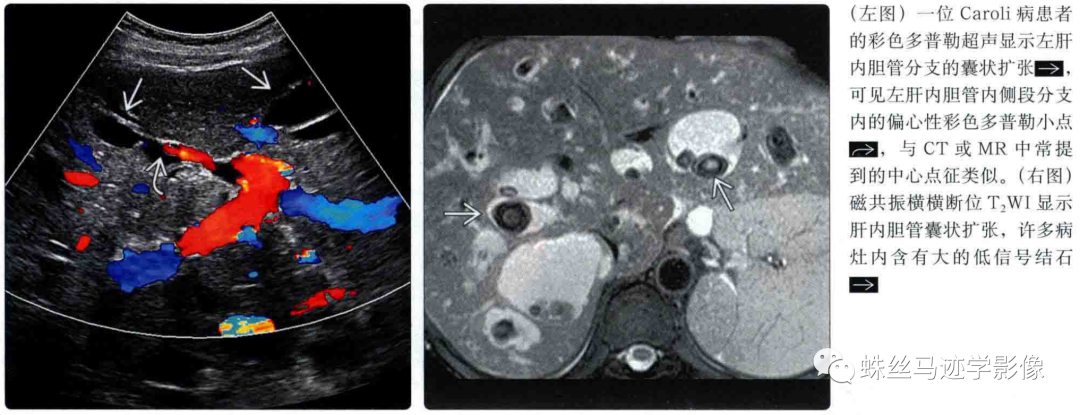

肝内胆管错构瘤和先天性肝内胆管囊状扩张症(Caroli病)-4